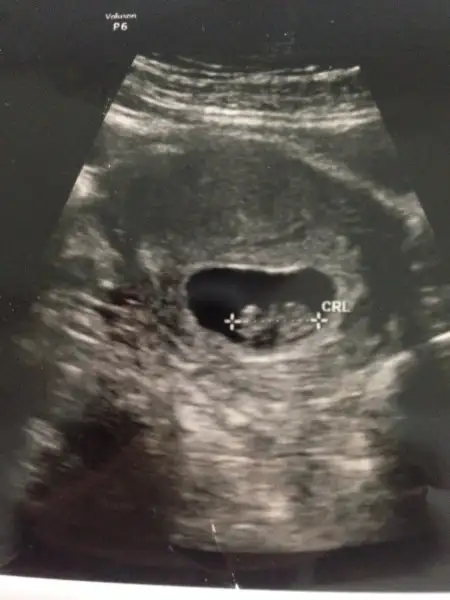

kız gibi canım. Şöyle usg resmini eline aldığında eğer karından usg ise bebek kesenin sağına yakınsa kız soluna yakınsa erkek, vajinal usg ise tam tersi. Buarada sesin ultrason resmi benimkine çok benziyo bebeğin kesedeki konumu olarak

Kizlar bugun tekrar gittim doktora,8 haftalikken bebek kesenin sagindaydi.simdi 10 haftalik,cok kipirdak sanirim sola yaklasmis.bu kese ve cinsiyet konusu kac haftalikken dogru oluyor? Bidaha bakarmisniz bana